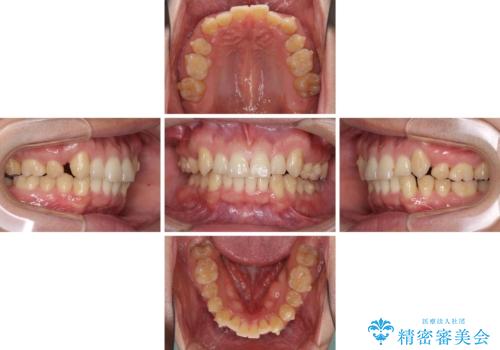

- 上顎の八重歯と前歯のデコボコを気にして来院された患者様です。

八重歯の移動量が多く、インビザライン単体での治療は困難と判断し、補助装置により八重歯移動後にインビザラインを用いることとしました。

治療途中で遠方に転勤となったため、通院が困難となり治療期間が長期化してしまいました。

上顎のみの抜歯矯正をインビザラインで行う場合、奥歯の前方移動がインビザラインでは苦手のため、奥歯の咬み合わせが不十分となることがあります。

今回の治療では終了時に奥歯は接触しているものの、接触の程度は物足りないものがある状態でした。今後保定期間に少しずつ奥歯の咬合を改善させていくことになります。